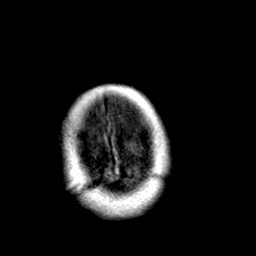

Creutzfeld-Jakob disease: gadolinium enchanced T1-Weighted MR -- Slice #23

[Home][Help][Clinical] Slice 23